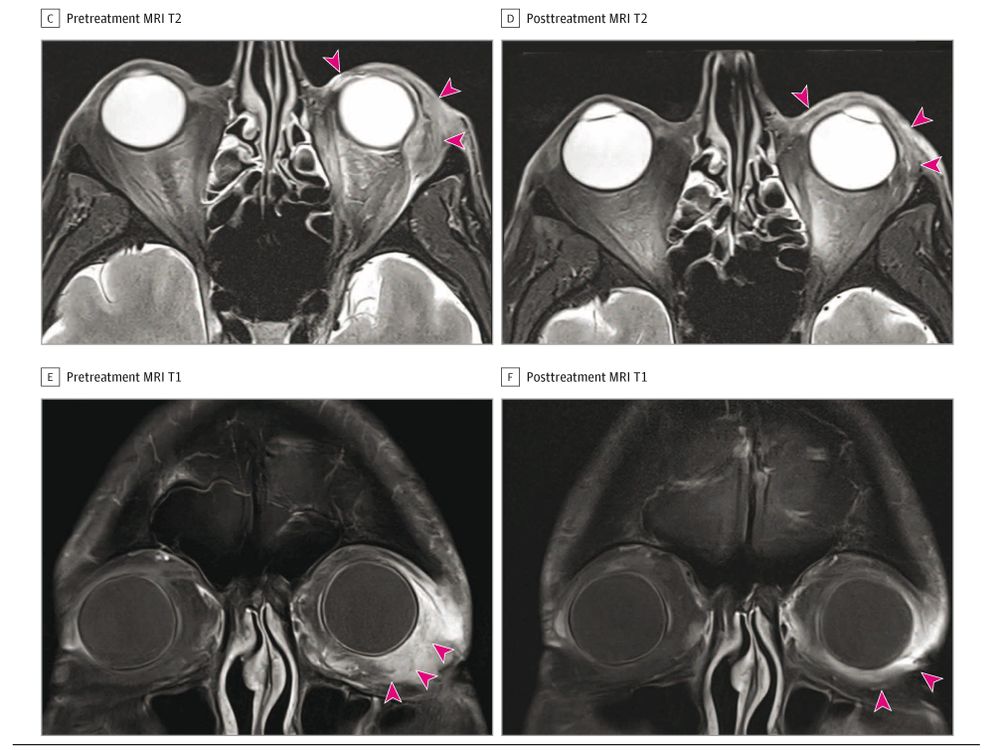

ja.ma/4pwroES

ja.ma/4pwroES

What would you do next?

ja.ma/4836CXO

What would you do next?

ja.ma/4836CXO